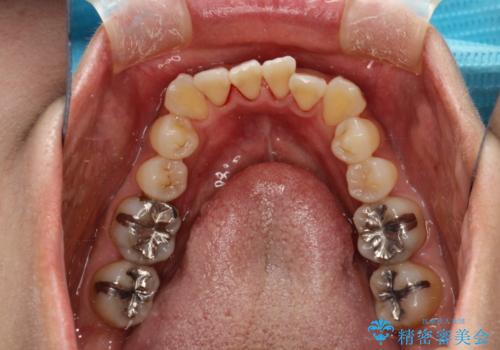

矯正治療が始まる前に歯のお掃除

- これから矯正治療を始めるため、今の状態でも歯をきれいにしておきたいとのことでした。PMTC60分コースを行いました。

プラーク(細菌の塊)や歯石がたまると歯の表面はザラつきいてきます。そのザラつきは歯周病や虫歯菌の棲家となります。そのまま放置すると、歯肉が腫れてきたり、歯肉から出血したり、口臭が強くでたりします。とくに歯肉の境目は、歯磨きで汚れを除去することが難しく、プラーク(細菌の塊)や歯石が溜まりやすい場所です。

歯並が、がたついている場合はなおさら汚れが溜まりやすいです。矯正治療前や矯正中、定期的にPMTCをすることで、矯正治療中の歯肉トラブルを防ぐことにつながります。